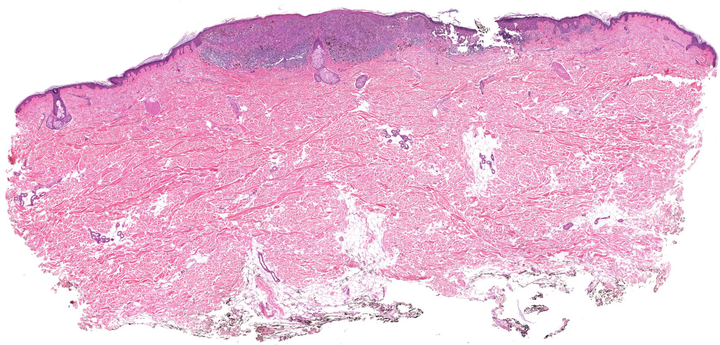

We have developed various image analysis approaches in the context of skin and breast cancer, based on histology images obtained via tissue biopsies. In many cases tissue suptypes are of interest which can, for example, be defined from genomics or derived from image characteristics. This is an ideal playground to develop new image analysis methods for microscopy, for example, to 1) extract cellular and nuclear features, to 2) assess large-scale architectonic arrangements, 3) to relate image characteristics to survival and recurrence, and 4) to develop methods with the potential for clinical impact on diagnosis and treatment.